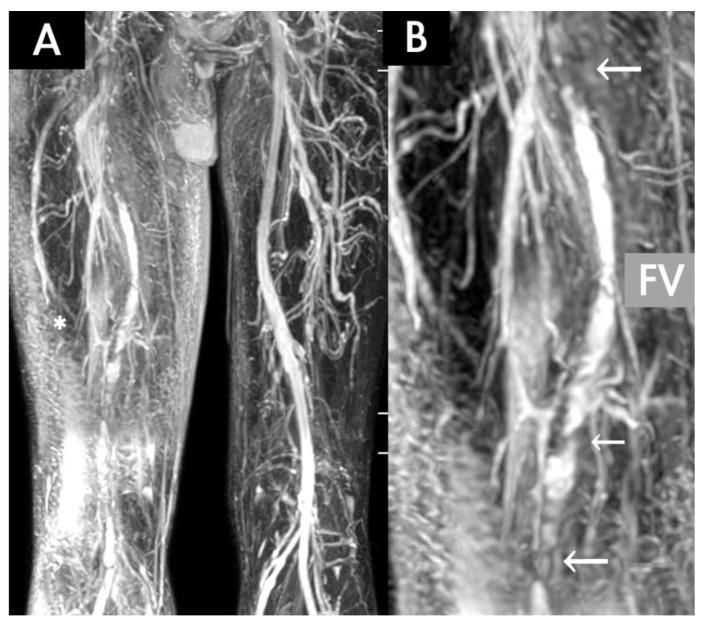

Between April 2017 and June 2019, 66 patients were evaluated for venous diseases through TRANCE-magnetic resonance imaging (MRI) and were grouped according to whether they had occlusive venous (OV) disease, a static venous ulcer (SU), or symptomatic varicose veins (VV). The clinical appliance of TRANCE-MRI was analysed by groups.

RESULTS

In total, 63 patients completed the study. TRANCE-MRI could identify venous thrombosis, including that of the abdominal and pelvic vessels, and it enabled the timely treatment of underlying diseases in patients with OV disease. TRANCE-MRI was statistically compared with the duplex scan, the gold standard to exclude deep vein thrombosis (DVT) in the legs, with regard to their abilities to detect venous thrombosis by using Cohen's kappa coefficient at a compatible value of 0.711. It could provide the occlusion degree of the peripheral artery for treating an SU. Finally, TRANCE-MRI can be used to outline all collateral veins and occult thrombi before treating symptomatic or recurrent VV to ensure a perfect surgical plan and to avoid complications.

2017年4月至2019年6月期间,66例患者通过TRANCE磁共振成像(MRI)评估静脉疾病,并根据是否患有闭塞性静脉(OV)疾病、静态静脉溃疡(SU)或有症状的静脉曲张(VV)进行分组。对TRANCE-MRI的临床应用进行分组分析。

结果

共有63例患者完成研究。TRANCE-MRI能够识别静脉血栓形成,包括腹部和盆腔血管的血栓形成,并能及时治疗OV疾病患者的基础疾病。将TRANCE-MRI与双功扫描(排除腿部深静脉血栓形成(DVT)的金标准)在检测静脉血栓形成能力方面进行统计学比较,使用Cohen's kappa系数,其兼容值为0.711。它可以为治疗SU提供外周动脉的闭塞程度。最后,在治疗有症状或复发性VV之前,TRANCE-MRI可用于勾勒所有侧支静脉和隐匿性血栓,以确保完美的手术方案并避免并发症。